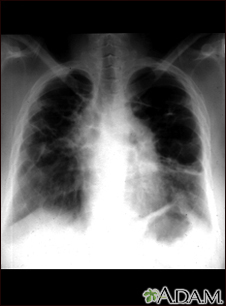

Sarcoid, stage IV - chest x-rayBackSarcoid, stage IV - chest x-rayThis film shows advanced sarcoid, scarring of the lungs (the light streaking), and cavity formation (the dark areas in the upper right side of the picture). E-mail FormEmail ResultsName:Email address:Recipients Name:Recipients address:Message: